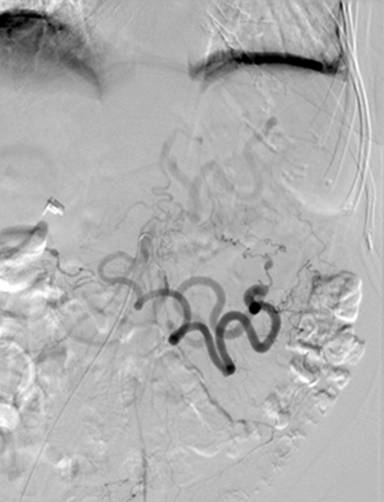

A 64-year-old Caucasian female was referred to our facility for further management of hemorrhagic pancreatitis. The patient had previously presented to an outside hospital with acute onset of severe sharp mid-abdominal pain, back pain, and nausea. She had no prior history of pancreatitis or alcohol use and had a prior cholecystectomy. Initial laboratory tests revealed a normal lipase, calcium, and triglyceride level. She had a history of hypertension, emphysema, depression, and spinal stenosis. She also had breast cancer 13 years prior, which had been treated by lumpectomy, chemotherapy, and radiation. Computed tomography (CT) scan displayed a heterogeneous fluid collection 14.3x11.2x10.0 cm and was interpreted as hemorrhagic pancreatitis involving the body and tail of the pancreas. Before admission to our hospital, she had required intensive care unit support including intravenous antibiotics and a transfusion of one unit packed red blood cells. She was started on total parenteral nutrition and took nothing by mouth. After seven days of support, she continued to have abdominal pain and was referred to our institution. Upon arrival to our facility, the patient was hemodynamically stable and afebrile. A repeat CT of the abdomen with intravenous contrast was performed at our facility 17 days after initial outside presentation (Figure 1), and it demonstrated a heterogeneous fluid collection 9.1x5.8 cm in the anterior pararenal space inferior to pancreatic tail, which likely represented a hematoma. There was also a 6 mm small pseudoaneurysm within the central portion of the fluid collection. There was no evidence of pancreatitis. An angiogram was subsequently performed and demonstrated dilatations and strictures with multiple pseudoaneurysms in the branches of the superior mesenteric artery, inferior mesenteric artery, ileal colic artery, and hepatic arteries, with one being adjacent to the pancreas (Figures 2 and 3). An attempt to embolize the pseudoaneurysm within the hematoma was unsuccessful due to tortuous mesenteric arteries. Other laboratory data obtained included C-reactive protein at 36 mg/L (reference range: 0-8.0 mg/L) and erythrocyte sedimentation rate of 72 mm/h (reference range: 0-29 mm/h). The workup for vasculitis included anti-nuclear antibodies, anti-citrullinated protein antibodies, rheumatoid factor, anti-double stranded DNA antibodies, and complement levels, all of which were within reference limits. Proteinase antibodies and myeloperoxidase antibodies were also negative. Her leukocyte count was not elevated and blood cultures were negative for growth. There was no history of congenital vascular disorders. She had no skin lesions and no renal or neurological abnormalities. A diagnosis of segmental arterial mediolysis was given based on exclusion and imaging. The patient was monitored in the hospital setting for 6 days after transfer and remained hemodynamically stable. Once abdominal pain resolved and the patient was tolerating a regular diet, she was discharged with close follow-up. A CT angiogram conducted four (Figure 4) and eleven months later (Figure 5) revealed resolution of mesenteric pseudoaneurysms and peripancreatic hematoma.

Figure 2. Inferior mesenteric angiogram demonstrating large collateral with pseudoaneurysm of a small colic branch corresponding to the pseudoaneurysm seen on CT.